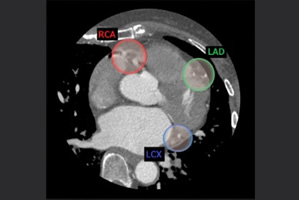

201704_voice_img_ct_02_03.jpg

図2. Smart Phase概念

201704_voice_img_ct_02_04.jpg

図3. Smart Phase

3本の独立した冠動脈をそれぞれ抽出し、そのアーチファクト量から自動で最適静止位相を検索する機能であり、画像処理時間の大幅な短縮が可能となった。(図2、3)